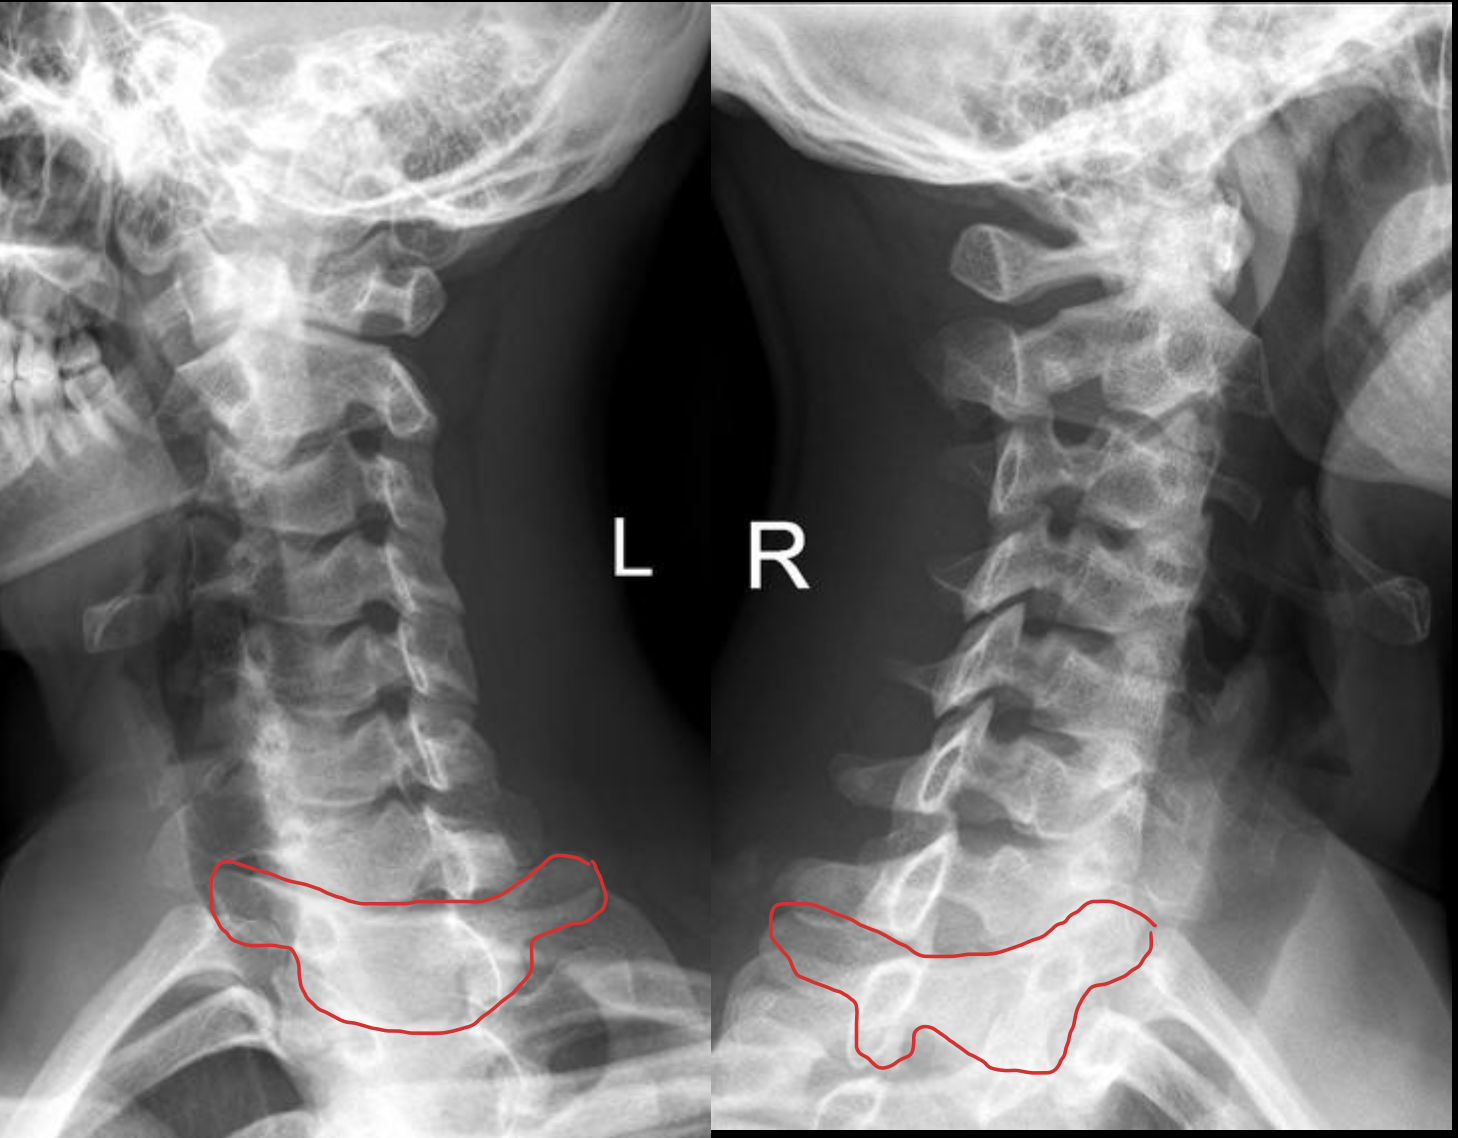

c7

T1

1ST Rib